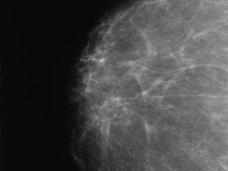

Many Women with Dense Breasts May Not Need Additional Screening

Breast density is just one of several factors that should be taken into account in determining the need for additional cancer screening, study suggests.